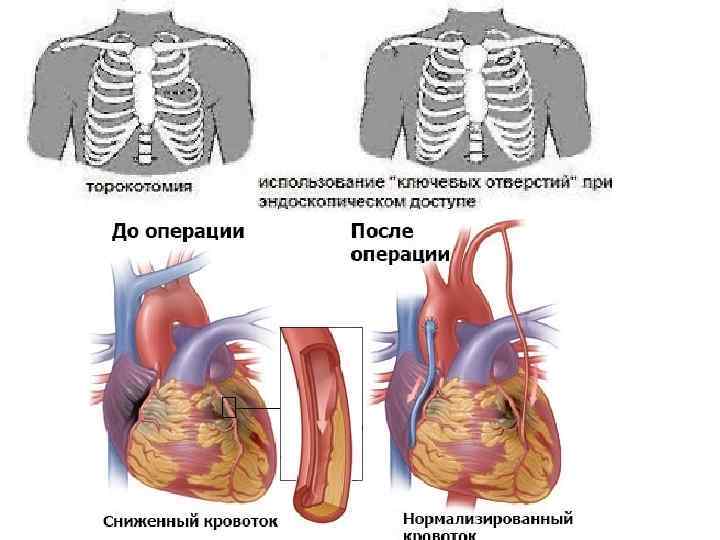

Миокард реваскуляризация әдісі АКШ – зақымдалған тәж артреиясынан айналып өту арқылы, айналма жол жасау Маммокоронарлы шунттау. Бұл кезде ішкі кеуда артреиясын пайдаланып, оны тәждік қанайналымға ауысытырады Аортакоронарлы шунттау. Бұл кезде бос кондуит н/е аутотрансплантантты пайдаланады. Дистальды бөлігін стеноздан төмен тәж артериясымен, ал проксимальды бөлігін аортаның жоғарылаған бөлігімен байланыстырады

Миокард реваскуляризация әдісі АКШ – зақымдалған тәж артреиясынан айналып өту арқылы, айналма жол жасау Маммокоронарлы шунттау. Бұл кезде ішкі кеуда артреиясын пайдаланып, оны тәждік қанайналымға ауысытырады Аортакоронарлы шунттау. Бұл кезде бос кондуит н/е аутотрансплантантты пайдаланады. Дистальды бөлігін стеноздан төмен тәж артериясымен, ал проксимальды бөлігін аортаның жоғарылаған бөлігімен байланыстырады